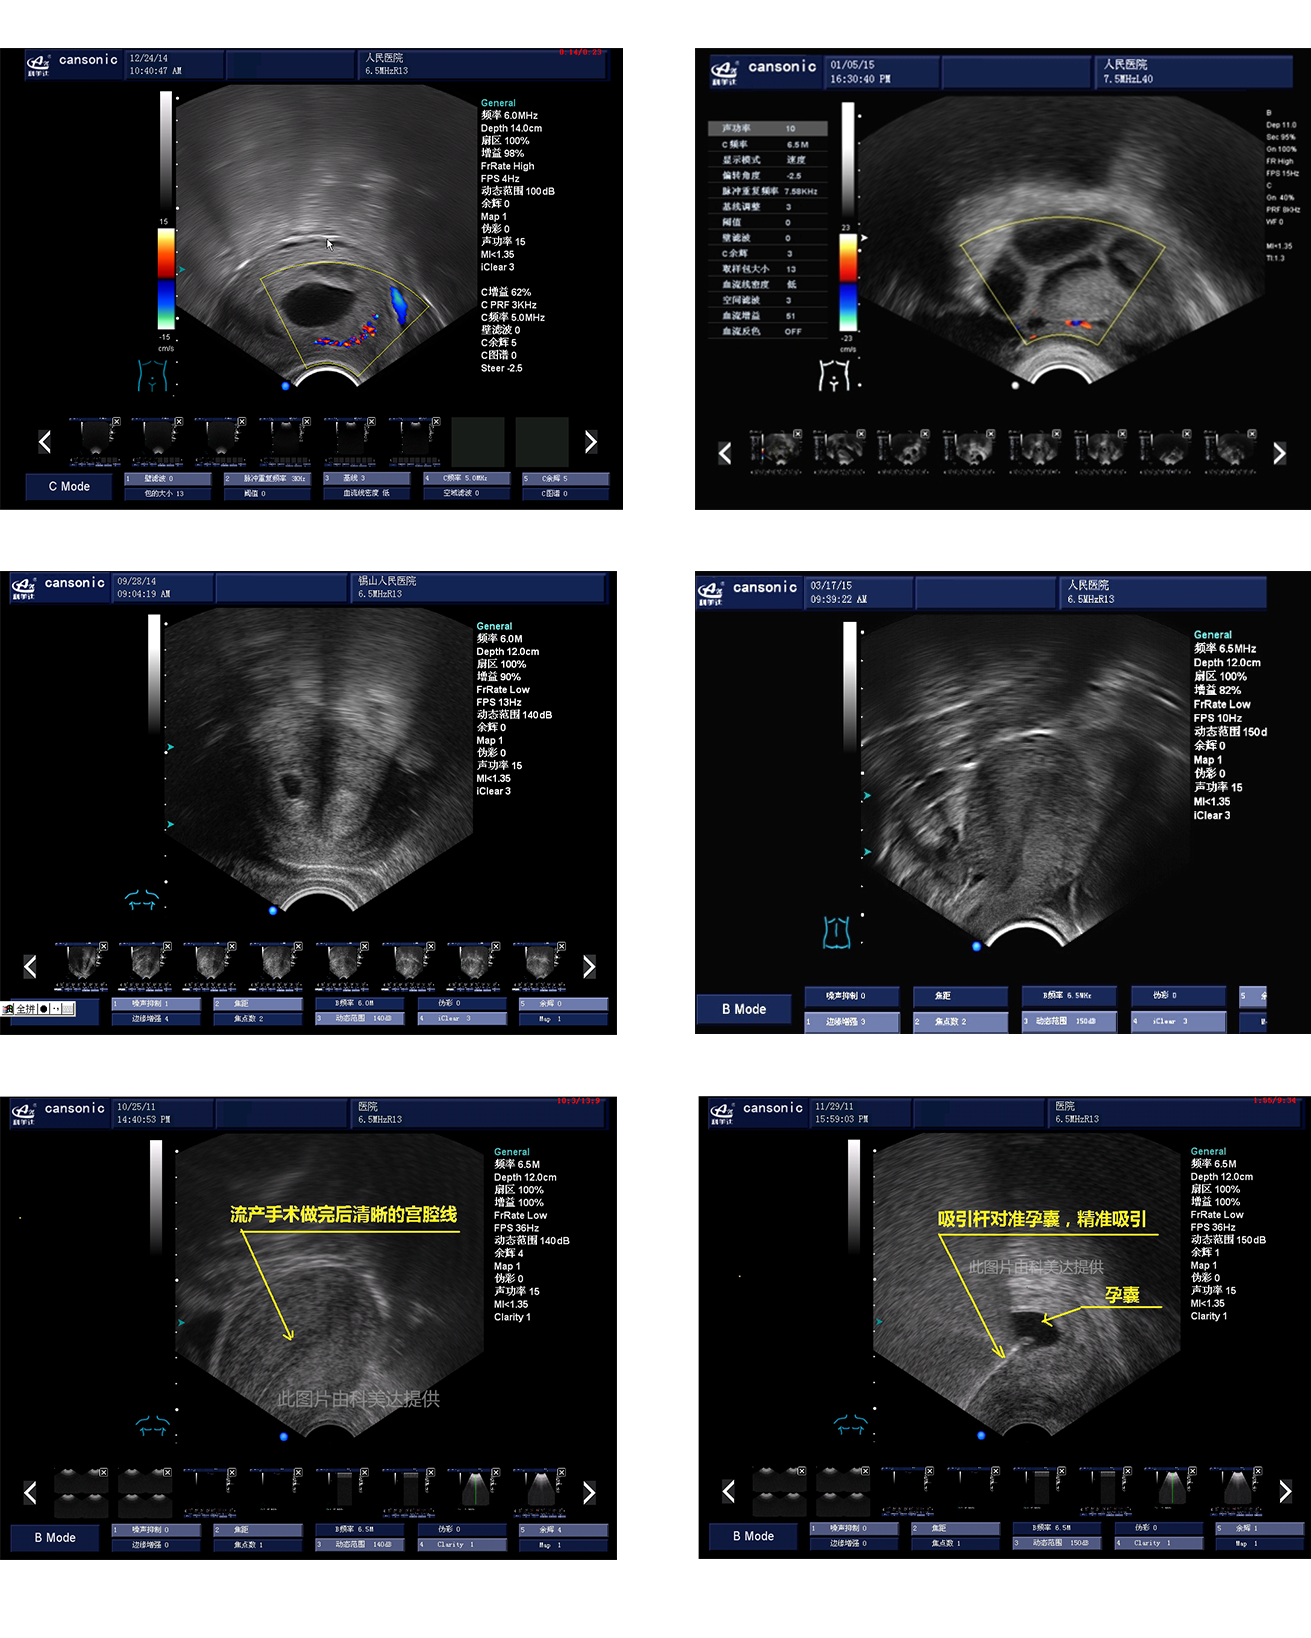

臨床圖示

1、薈萃前沿彩超技術,使得超聲監測與手術操作完美融合,實現宮腔手術的全程監測

2、復合成像技術,增強組織回聲,減少回聲失落,得到清晰、真實的手術影像

3、血流靈敏度高,清晰可見